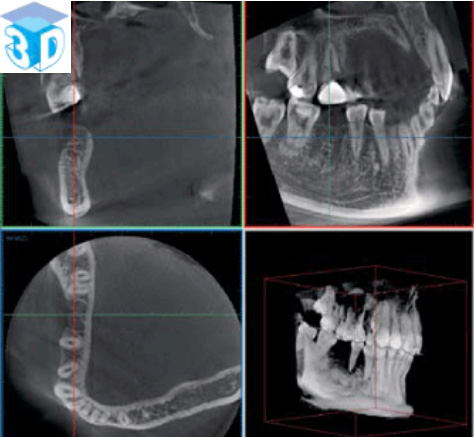

上図のような歯科用CTから得られる三次元的情報は、インプラント治療、歯周病治療、根管治療親知らずの抜歯など歯科治療のあらゆる分野での診断に必要不可欠なものとなってきています。詳しくはGCホームページをご覧ください。